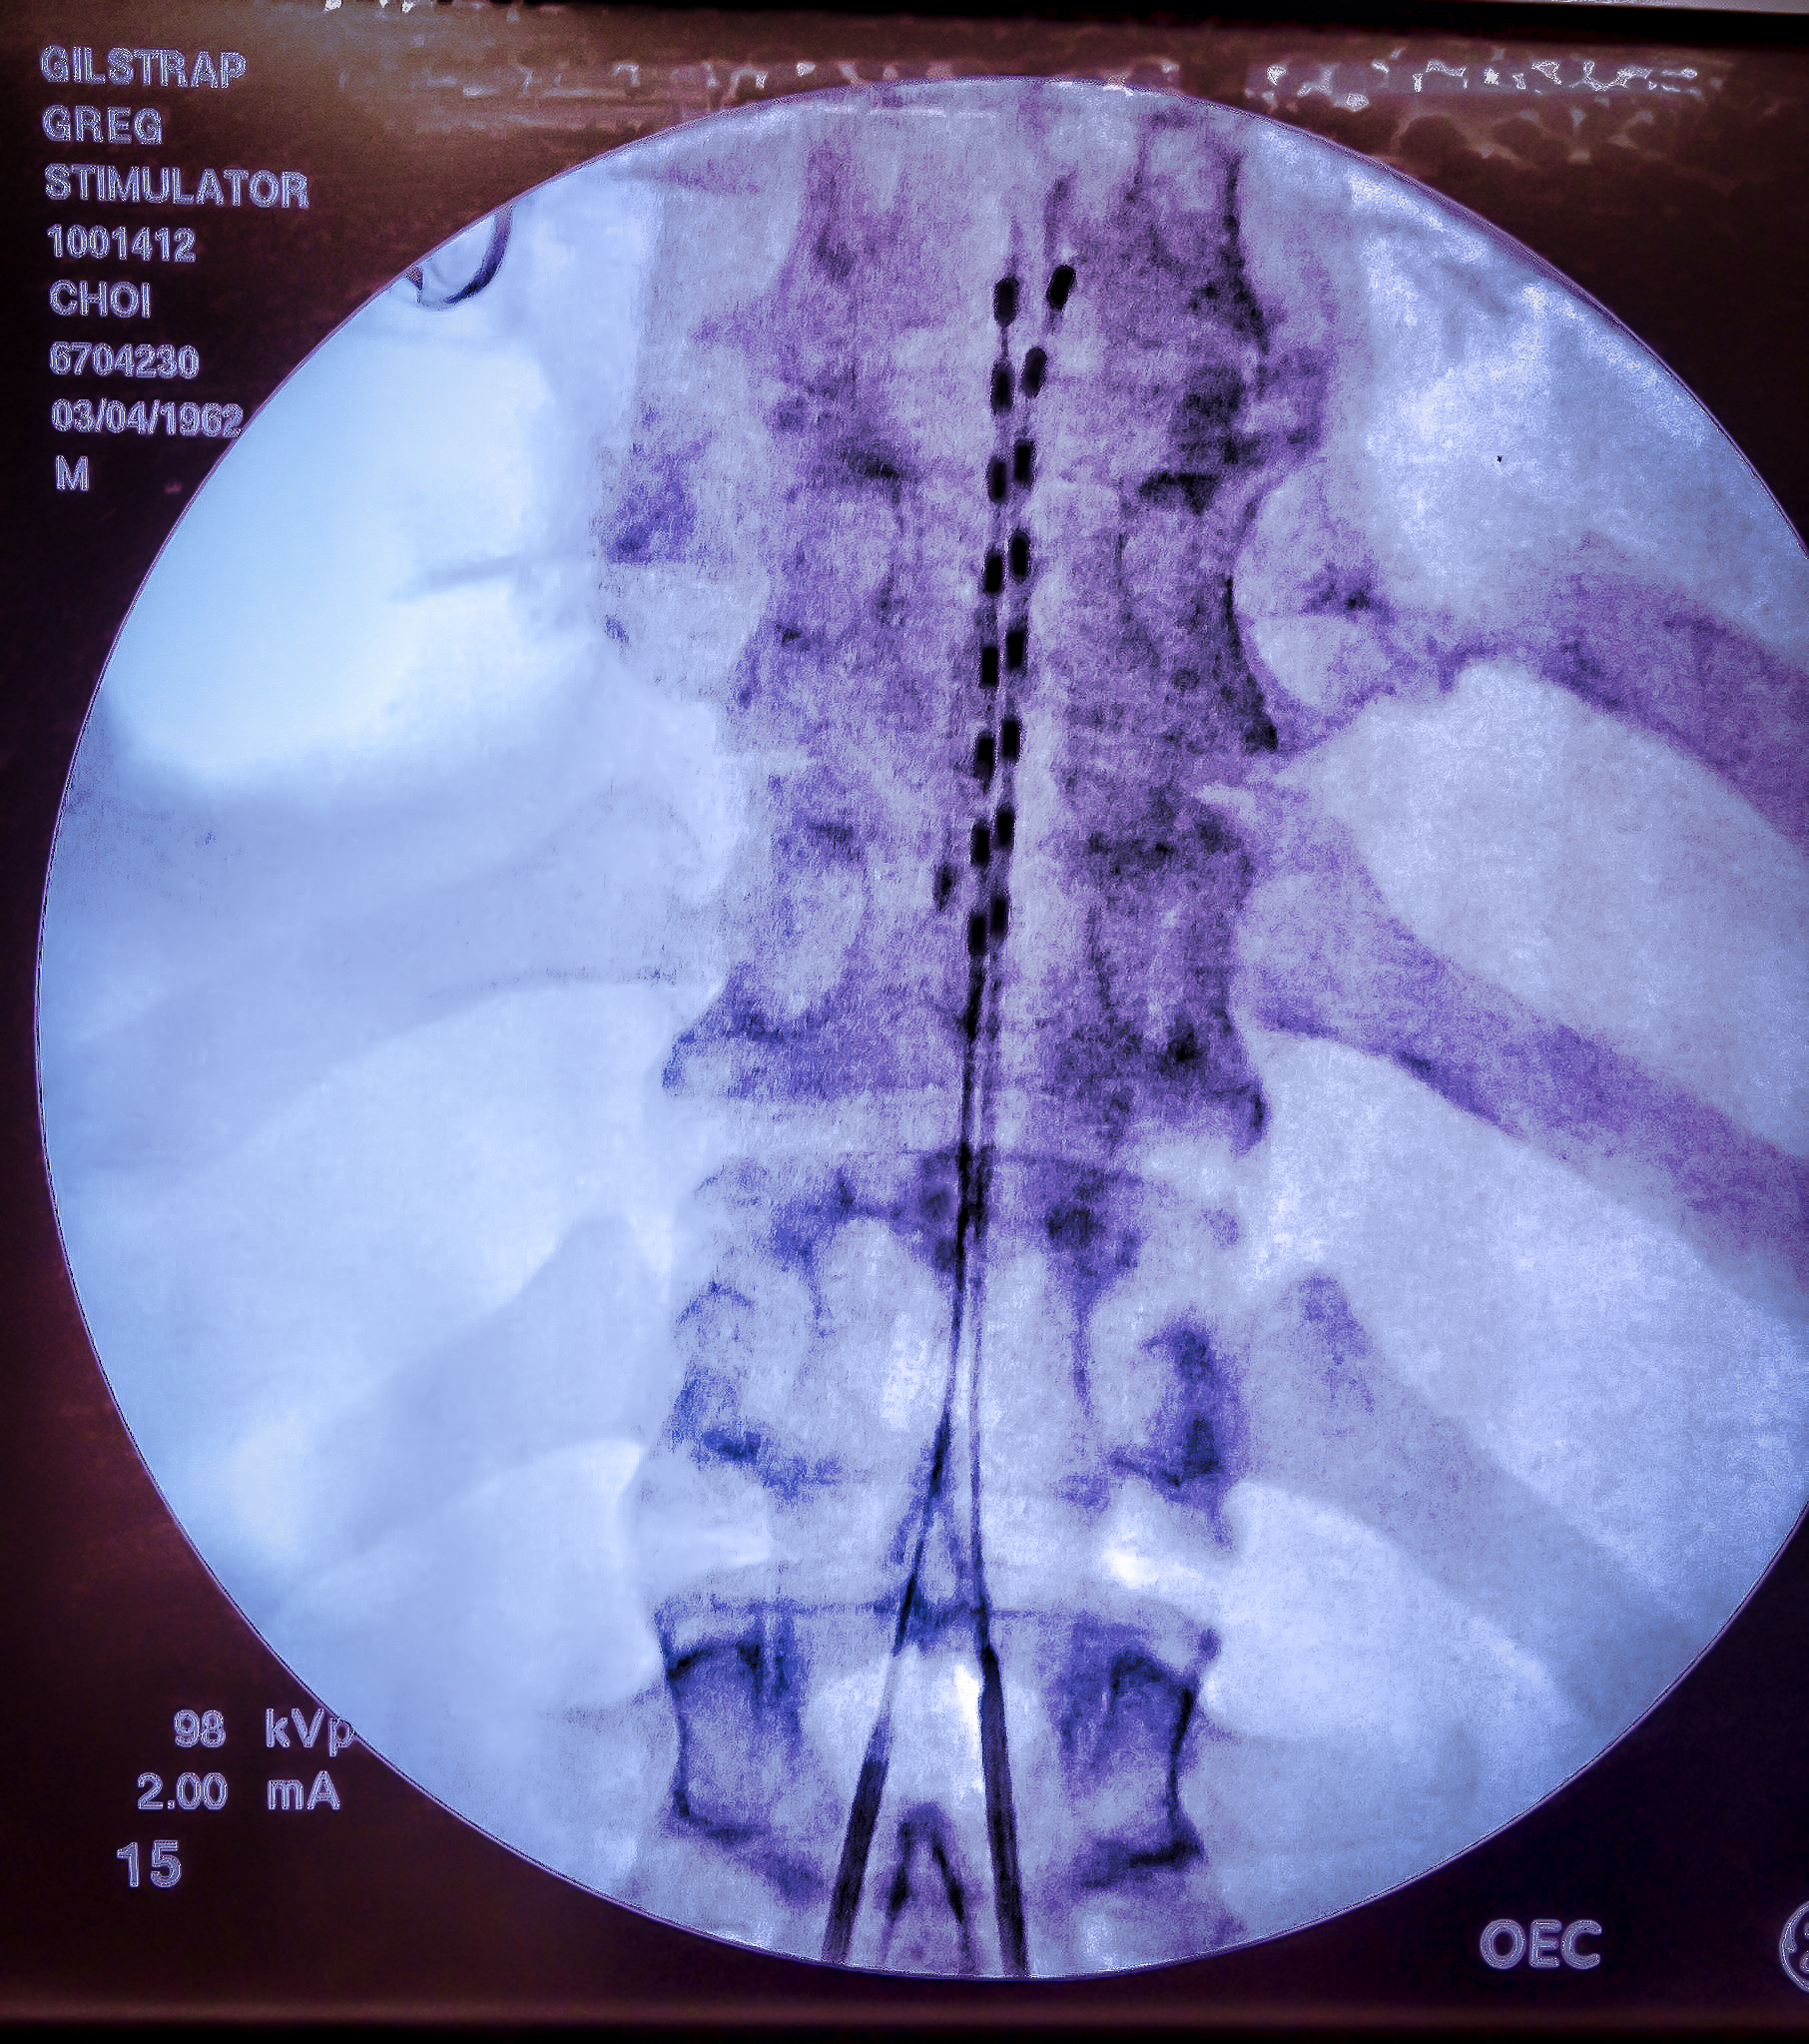

I was awake for nearly all of the approximately 200 minute procedure, but I was not able to see just how involved the surgery was. For those considering neurostimulators, do not let the photo below scare you. They gave me really good meds. There was little to no pain involved and you need to be awake to help them best direct the placement of the electrodes. As those who know me might expect, I even thought I had some of my best stand up lines going while they were doing this. The key word is “thought.”

I am a long ways from a final determination of how much elevation I will get from having two neurostimulators implanted under the skin on my backside and 32 electrodes running up and down my spine, but here’s my initial read on how the surgery went.

The two implants are already producing encouraging results. The severe pain I have lived with for some time in my right arm and left leg has certainly declined. My toes–which more often than not have felt like a UFC fighter stomped on them before smashing them with a super sized sledgehammer–have been completely free of pain ever since the surgery. The toe pain was a result of nerve damage I suffered when I broke a vertebrae and wore away a disc or two in my lower back. Two major lumber surgeries did not result in any major pain level reduction or increase in the function of my left leg. It did, however, leave me with titanium screws and rods.